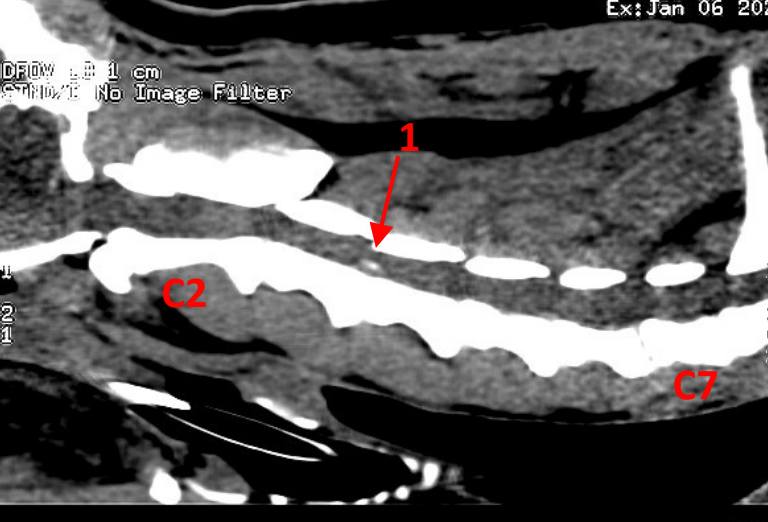

Hoje foi dia de cirurgia cervical.

É a terceira hérnia discal que operamos ao Baloo mas ele é um campeão.

Hora e meia depois da cirurgia "ventral slot" e já quer fugir da Pamela :_)

Na Bonematrix empenhamos todo o cuidado e rigor no tratamento de patologias de coluna.